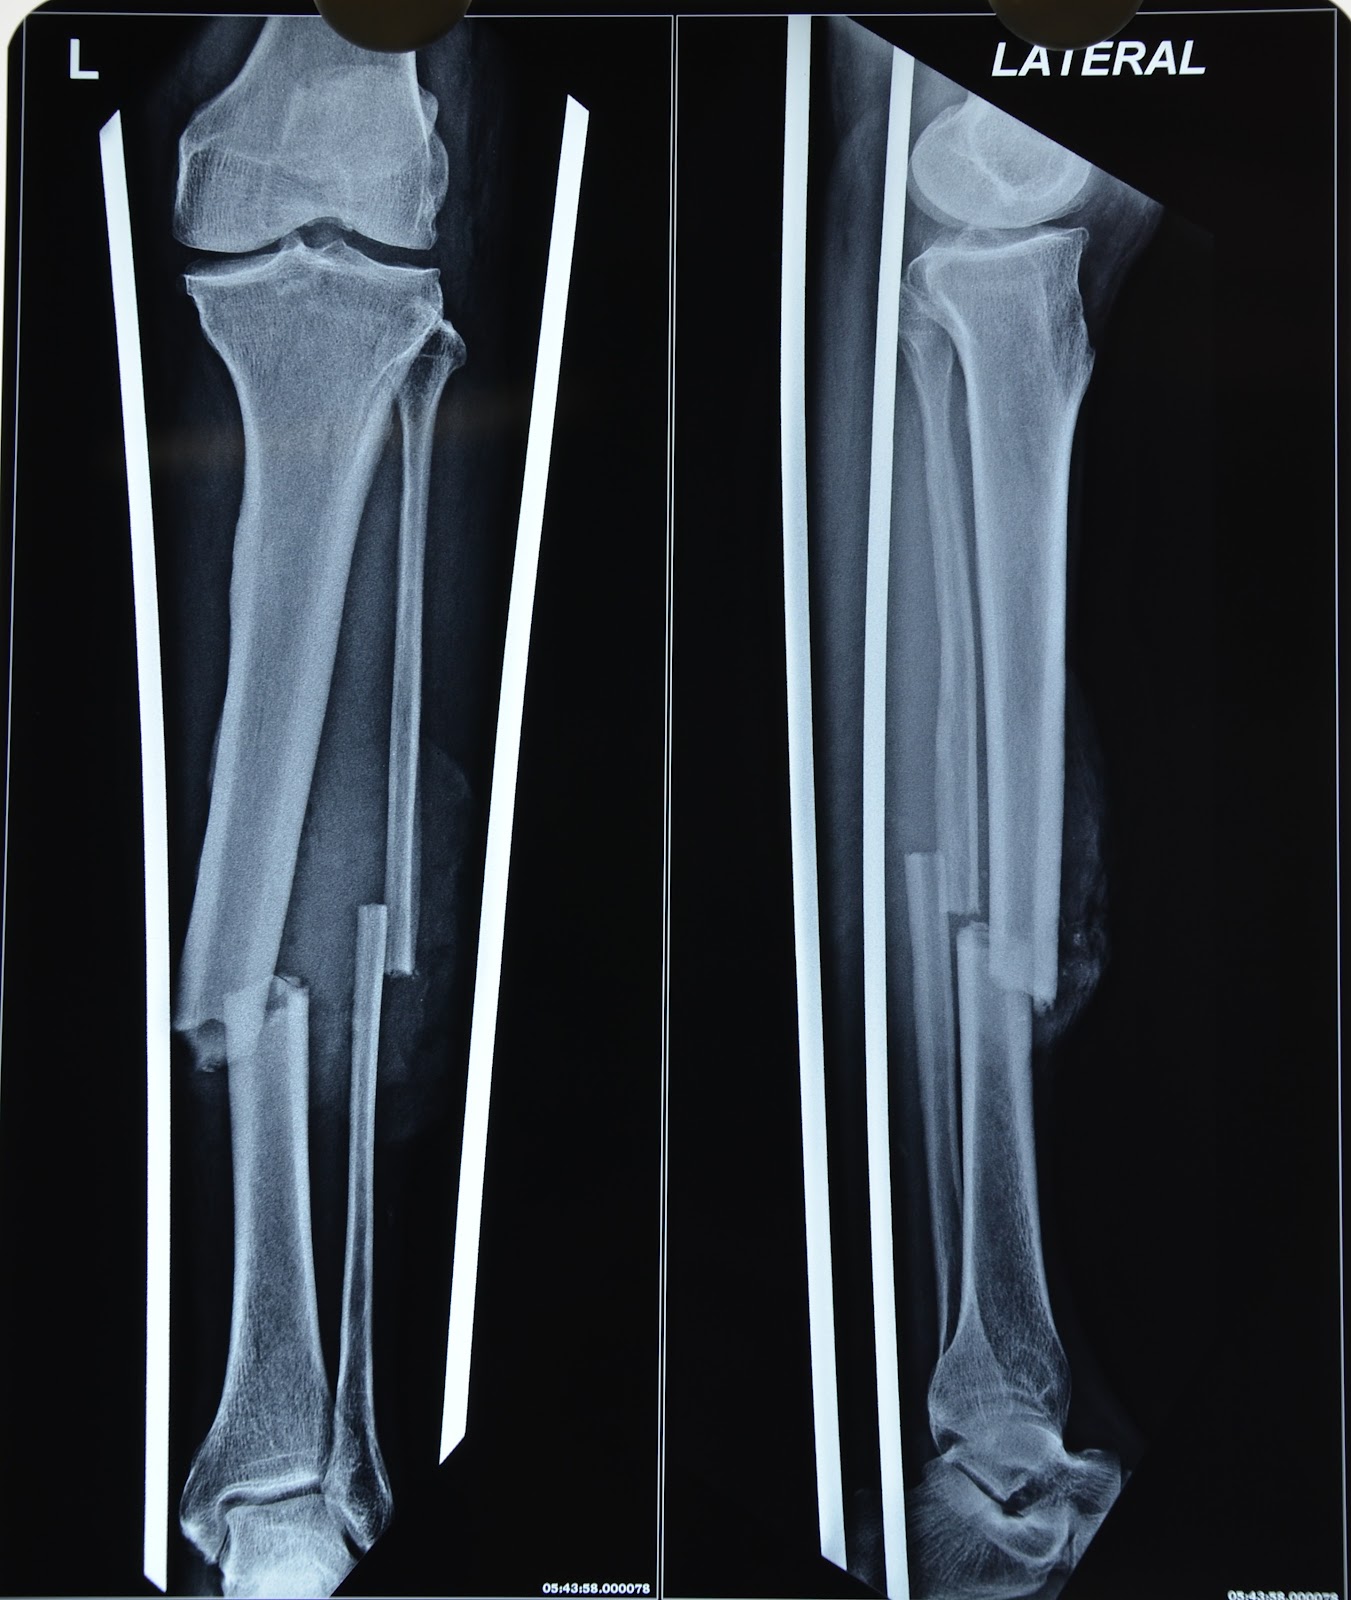

From roentgenrayreader.blogspot.co.uk

Roentgen Ray Reader Isolated Tibial Diaphysis Fractures Compression Fracture Tibia Treatment During this procedure, a specially designed metal. Making the vertebrae taller with a small balloon placed with a needle, then filling the empty space with a special cement. This article looks in detail at. treatment is generally operative with intramedullary nailing. our surgical options include: a break in the shinbone just below the knee is called a. Compression Fracture Tibia Treatment.